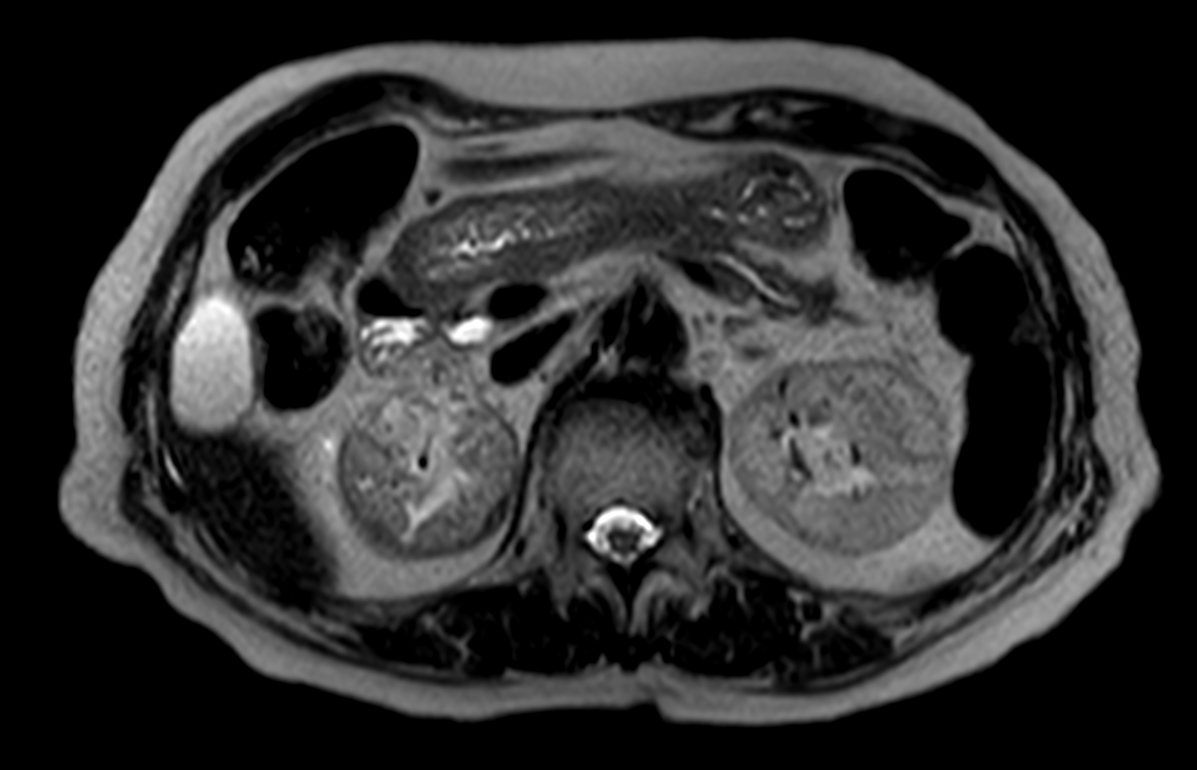

Patient with a kidney lesion. The ExamCard includes techniques for 3D imaging (PelvisVIEW, eTHRIVE) allowing for multiple image directions in one single scan, efficient fat-free imaging over large field-of-views (mDIXON XD), a multi-phase contrast-enhanced sequence (4D FreeBreathing) to improve imaging confidence and Compressed SENSE to accelerate the entire exam.

T2w TSE